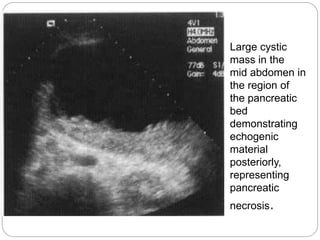

Large cystic mass inthe mid abdomen in the region of the pancreatic bed demonstrating echogenic material posteriorly, representing pancreatic necrosis.